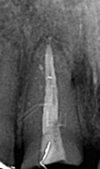

- Cas clinique 1 :

La racine de l’incisive centrale est fracturée et la couronne se descelle de plus en plus souvent. L’os alvéolaire est infecté depuis longtemps et contre-indique une extraction-implantation immédiate.

La radiographie montre une fracture oblique de la racine.